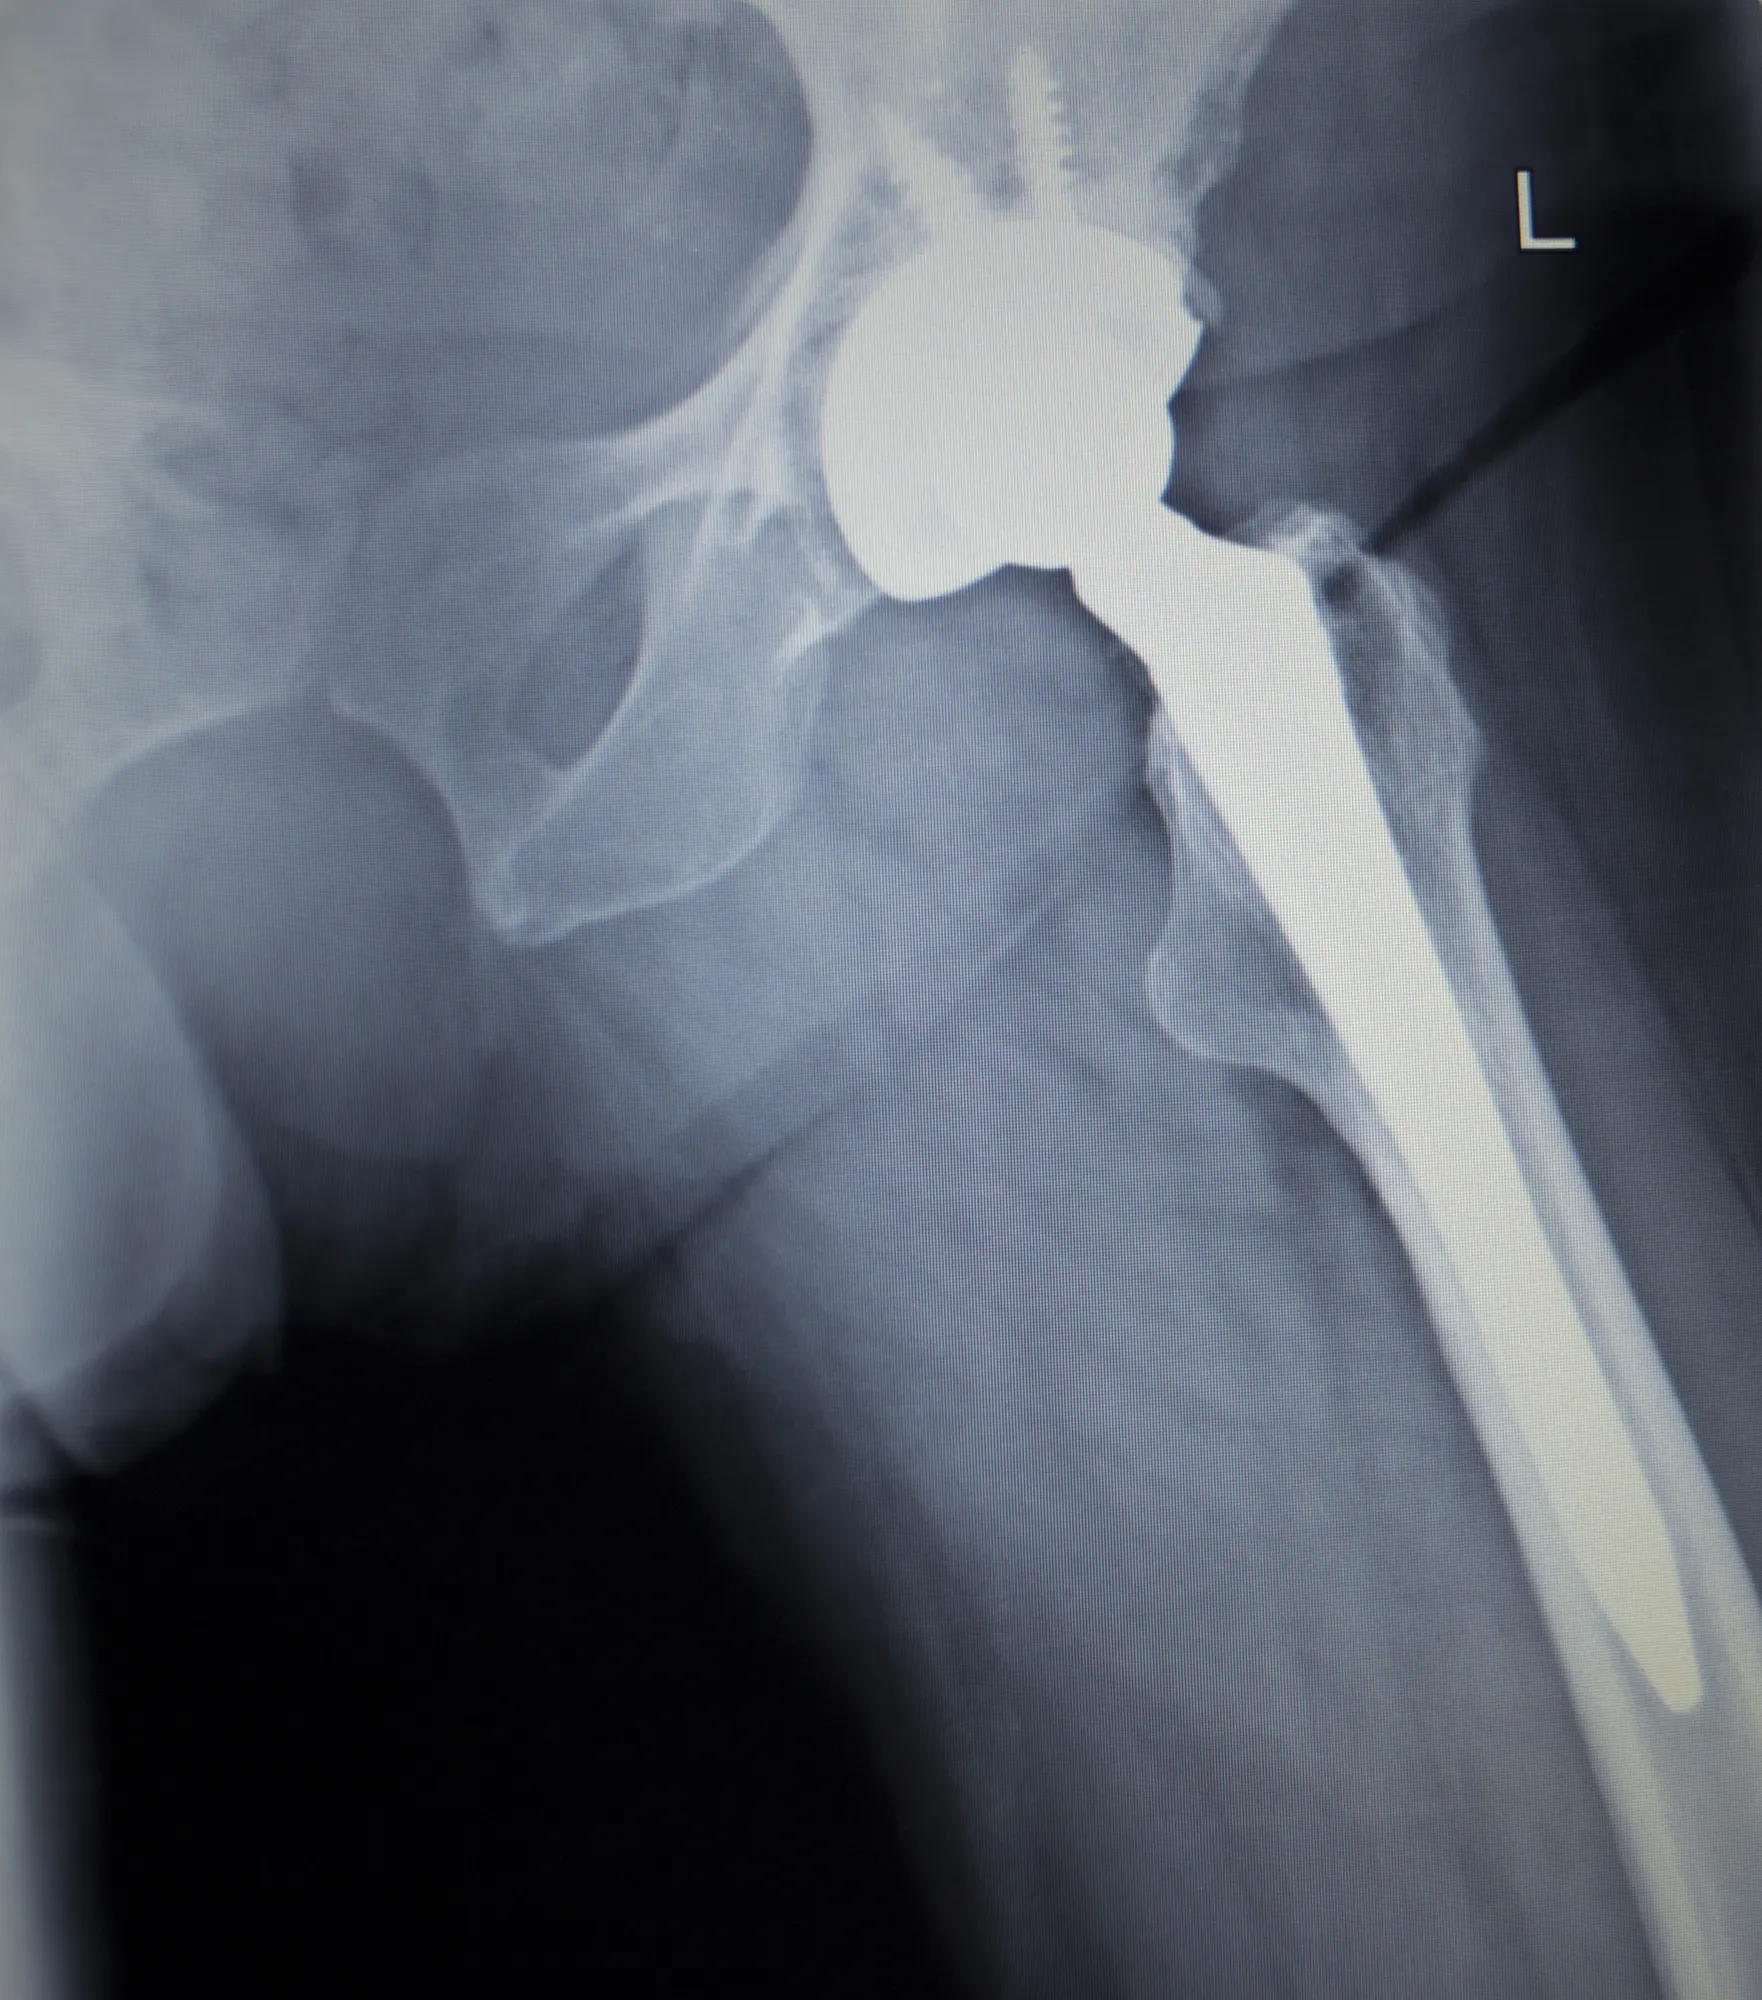

The Stryker hip replacement implants class action lawsuit alleged that defective artificial hips were implanted in Class Members and the Stryker Rejuvenate Modular Hip System was falsely advertised as a non metal-on-metal hip implant.

The class action lawsuit pointed out hip implant surgery has been in use for over 40 years and can be an effective way to treat diseases and injuries of the hip joint. However, metal-on-metal hip implants have a propensity to cause damage after being implanted. According to the complaint, the metal components rub together, fret, and corrode, releasing metal into the tissue. Problems with premature loosening, misalignment, fracture, dislocation, and failure have also been linked to metal-on-metal implants, alleged the plaintiffs.

Despite these problems, which have been known since the 1970s, Stryker designed a hip implant system that utilized metal components, the complaint claimed. The Stryker Rejuvenate Modular Hip System includes modular neck and stem components made of metal. These components rub together, causing patients issues, claimed the plaintiffs.

The Stryker hip replacement implants class action lawsuit further alleged that the Rejuvenate Modular Hip System was misleadingly marketed as a non-metal-on-metal because the product does not have a metal femoral head and liner. However, the metal components of the device did rub, alleged the complaint, causing the plaintiffs and proposed Class Members injury.

“The Stryker Implants all shared common defective design characteristics that made them susceptible to early failure and to cause serious adverse effects in patients,” contended the class action lawsuit. “The Stryker Implants are defective because their metal components have an unreasonable propensity to fret and corrode, releasing heavy debris into the surrounding tissue, causing premature component loosening, misalignment, dislocation, fracture, and implant failure.”